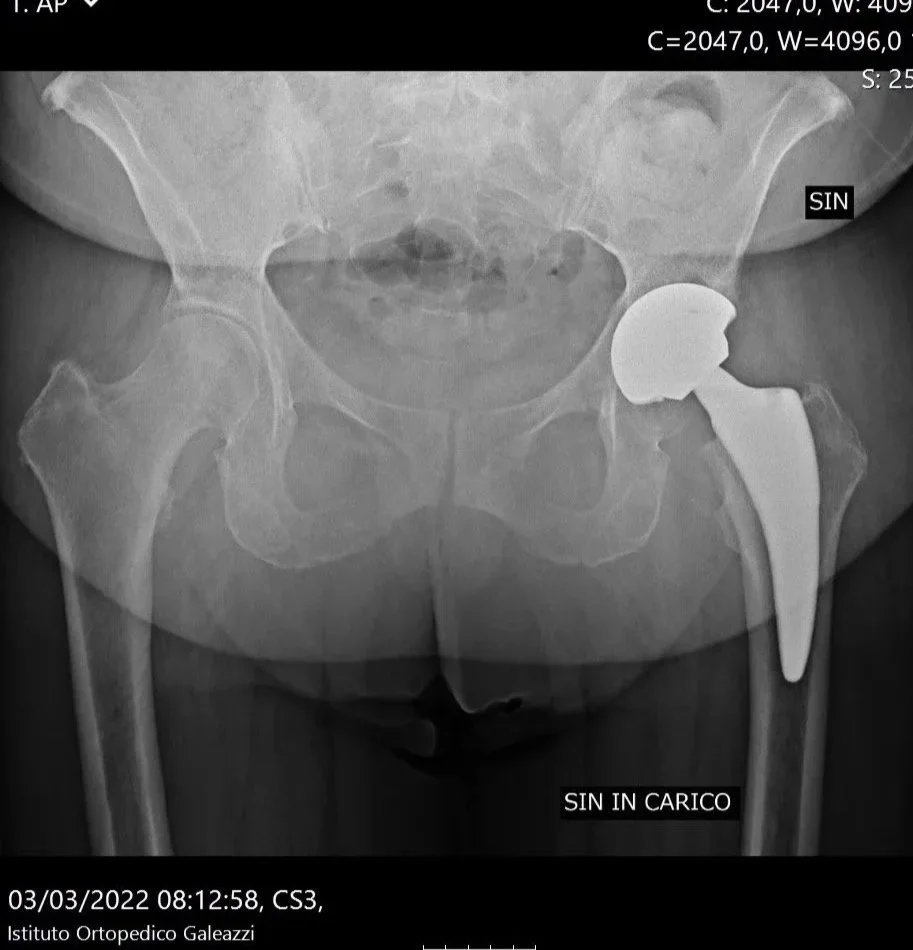

Radiografia del bacino che mostra una protesi d’anca destra. Immagine utilizzata per illustrare gli interventi di chirurgia protesica dell’anca eseguiti dal Dottor Fabrizio Bertelle.